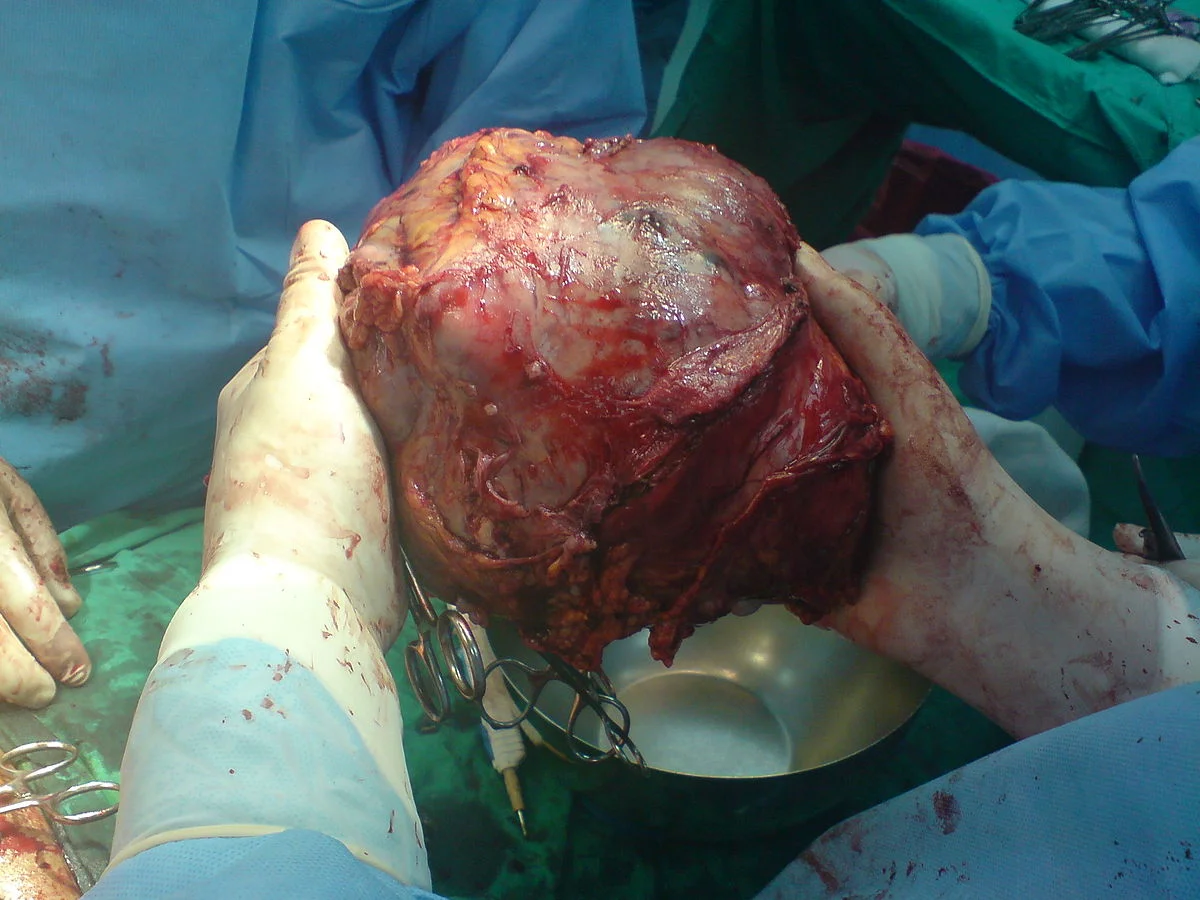

2. Increases The Chances of Developing Cancer

Alcohol increases your risk to develop certain cancers:

This is because acetaldehyde (metabolite from alcohol being broken down in the liver) damages genetic materials in the cells and renders them incapable of repairing the damage. R

It can also cause cells to grow too quickly, without checking for mistakes. R

When cells break down alcohol, they produce Vascular Endothelial Growth Factor (VEGF) promoting growth of blood vessels and organ tissue. R

When you have too much VEGF, it can cause tumors to grow exponentially. R

3. Damages The Liver

The liver breaks down most of the alcohol a person consumes. R

The process of breaking down alcohol generates toxins that are even more harmful than alcohol itself. R

These by-products damage liver cells, promote inflammation and weaken the body's natural defenses. R

- Liver Cancer R